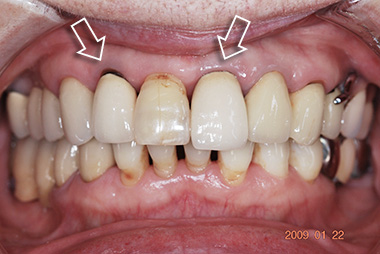

術前 閉口 全体像

メタルボンドをかぶせる前に、部分矯正にて歯肉のラインを改善しました。炎症が起こりにくく健康な歯肉を維持しやすくなりました。

術後 閉口 全体像

部分矯正にて歯肉のラインを改善してからメタルボンドをかぶせたことにより、炎症が起こりにくく、歯肉の健康を維持しやすくなりました。

また、かみ合わせを安定させるための咬合治療も行いました。

術前 上顎

術後 上顎

左上4番と右上4・5番はオールセラミックス。 左右6番はゴールドクラウンにて修復しました。

術前 下顎

術後 下顎

左右4番はオールセラミックスによる修復。 右下5番はゴールドクラウンにより修復しました。